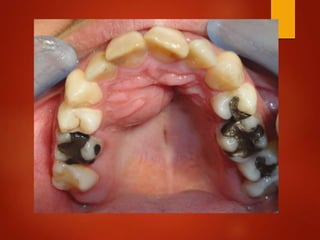

El documento es un registro médico odontológico que muestra las fechas de las visitas de un paciente al centro de salud El Raval, incluyendo exámenes y tratamientos realizados como la extracción de cálculos salivales en abril y mayo de 2012.